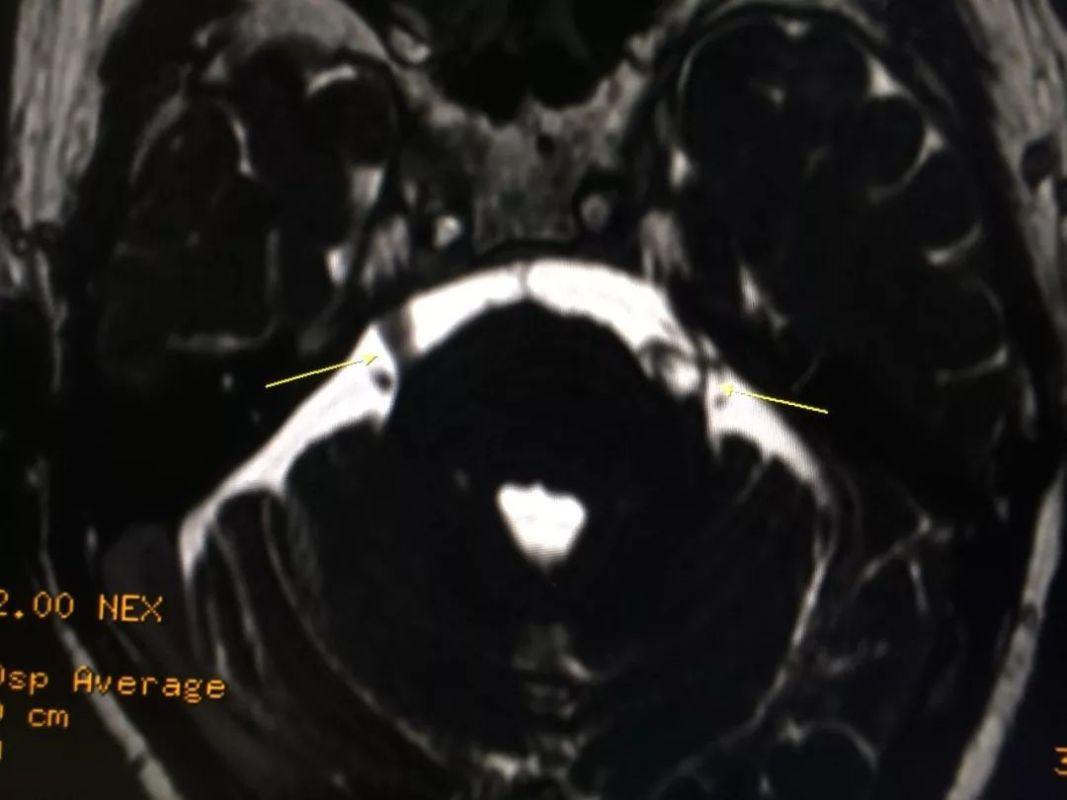

(2)蝶鞍区CT及MRI检查

在影像学上,鞍区 CT和 MRI是常用的检查手段,尤其优于 CT。